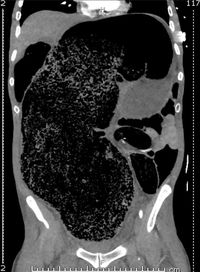

Hasil pindaian pada tubuhnya menunjukkan adanya setumpuk besar feses di ususnya. Tumpukan feses yang berjumlah 2 liter ini menekan keras arteri iliac kanan, merupakan pembuluh darah besar yang mengalirkan darah ke kaki kanannya.

Hasil pindaian menunjukkan ada 2 liter feses di usus Foto: BMJ Case Reports |

Hasil pindaian menunjukkan ada 2 liter feses di usus Foto: BMJ Case Reports